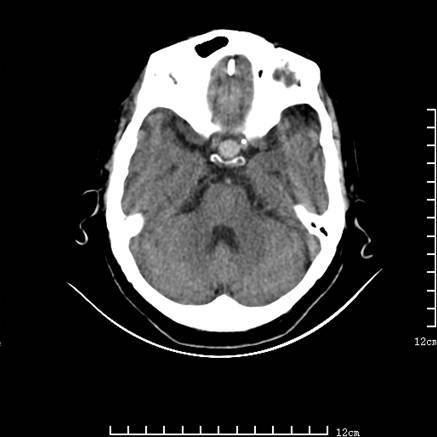

标题: V0514:女,72岁,偶有头晕,自诉记忆力减退,来诊。 [打印本页]

标题: V0514:女,72岁,偶有头晕,自诉记忆力减退,来诊。

1、考虑垂体腺瘤。

2、脑萎缩ct表现。

垂体腺瘤可能性大!另:轻度脑萎缩!

考虑垂体腺瘤可能性大。脑萎缩。

考虑垂体腺瘤可能性大。脑萎缩。  建议mri 检查